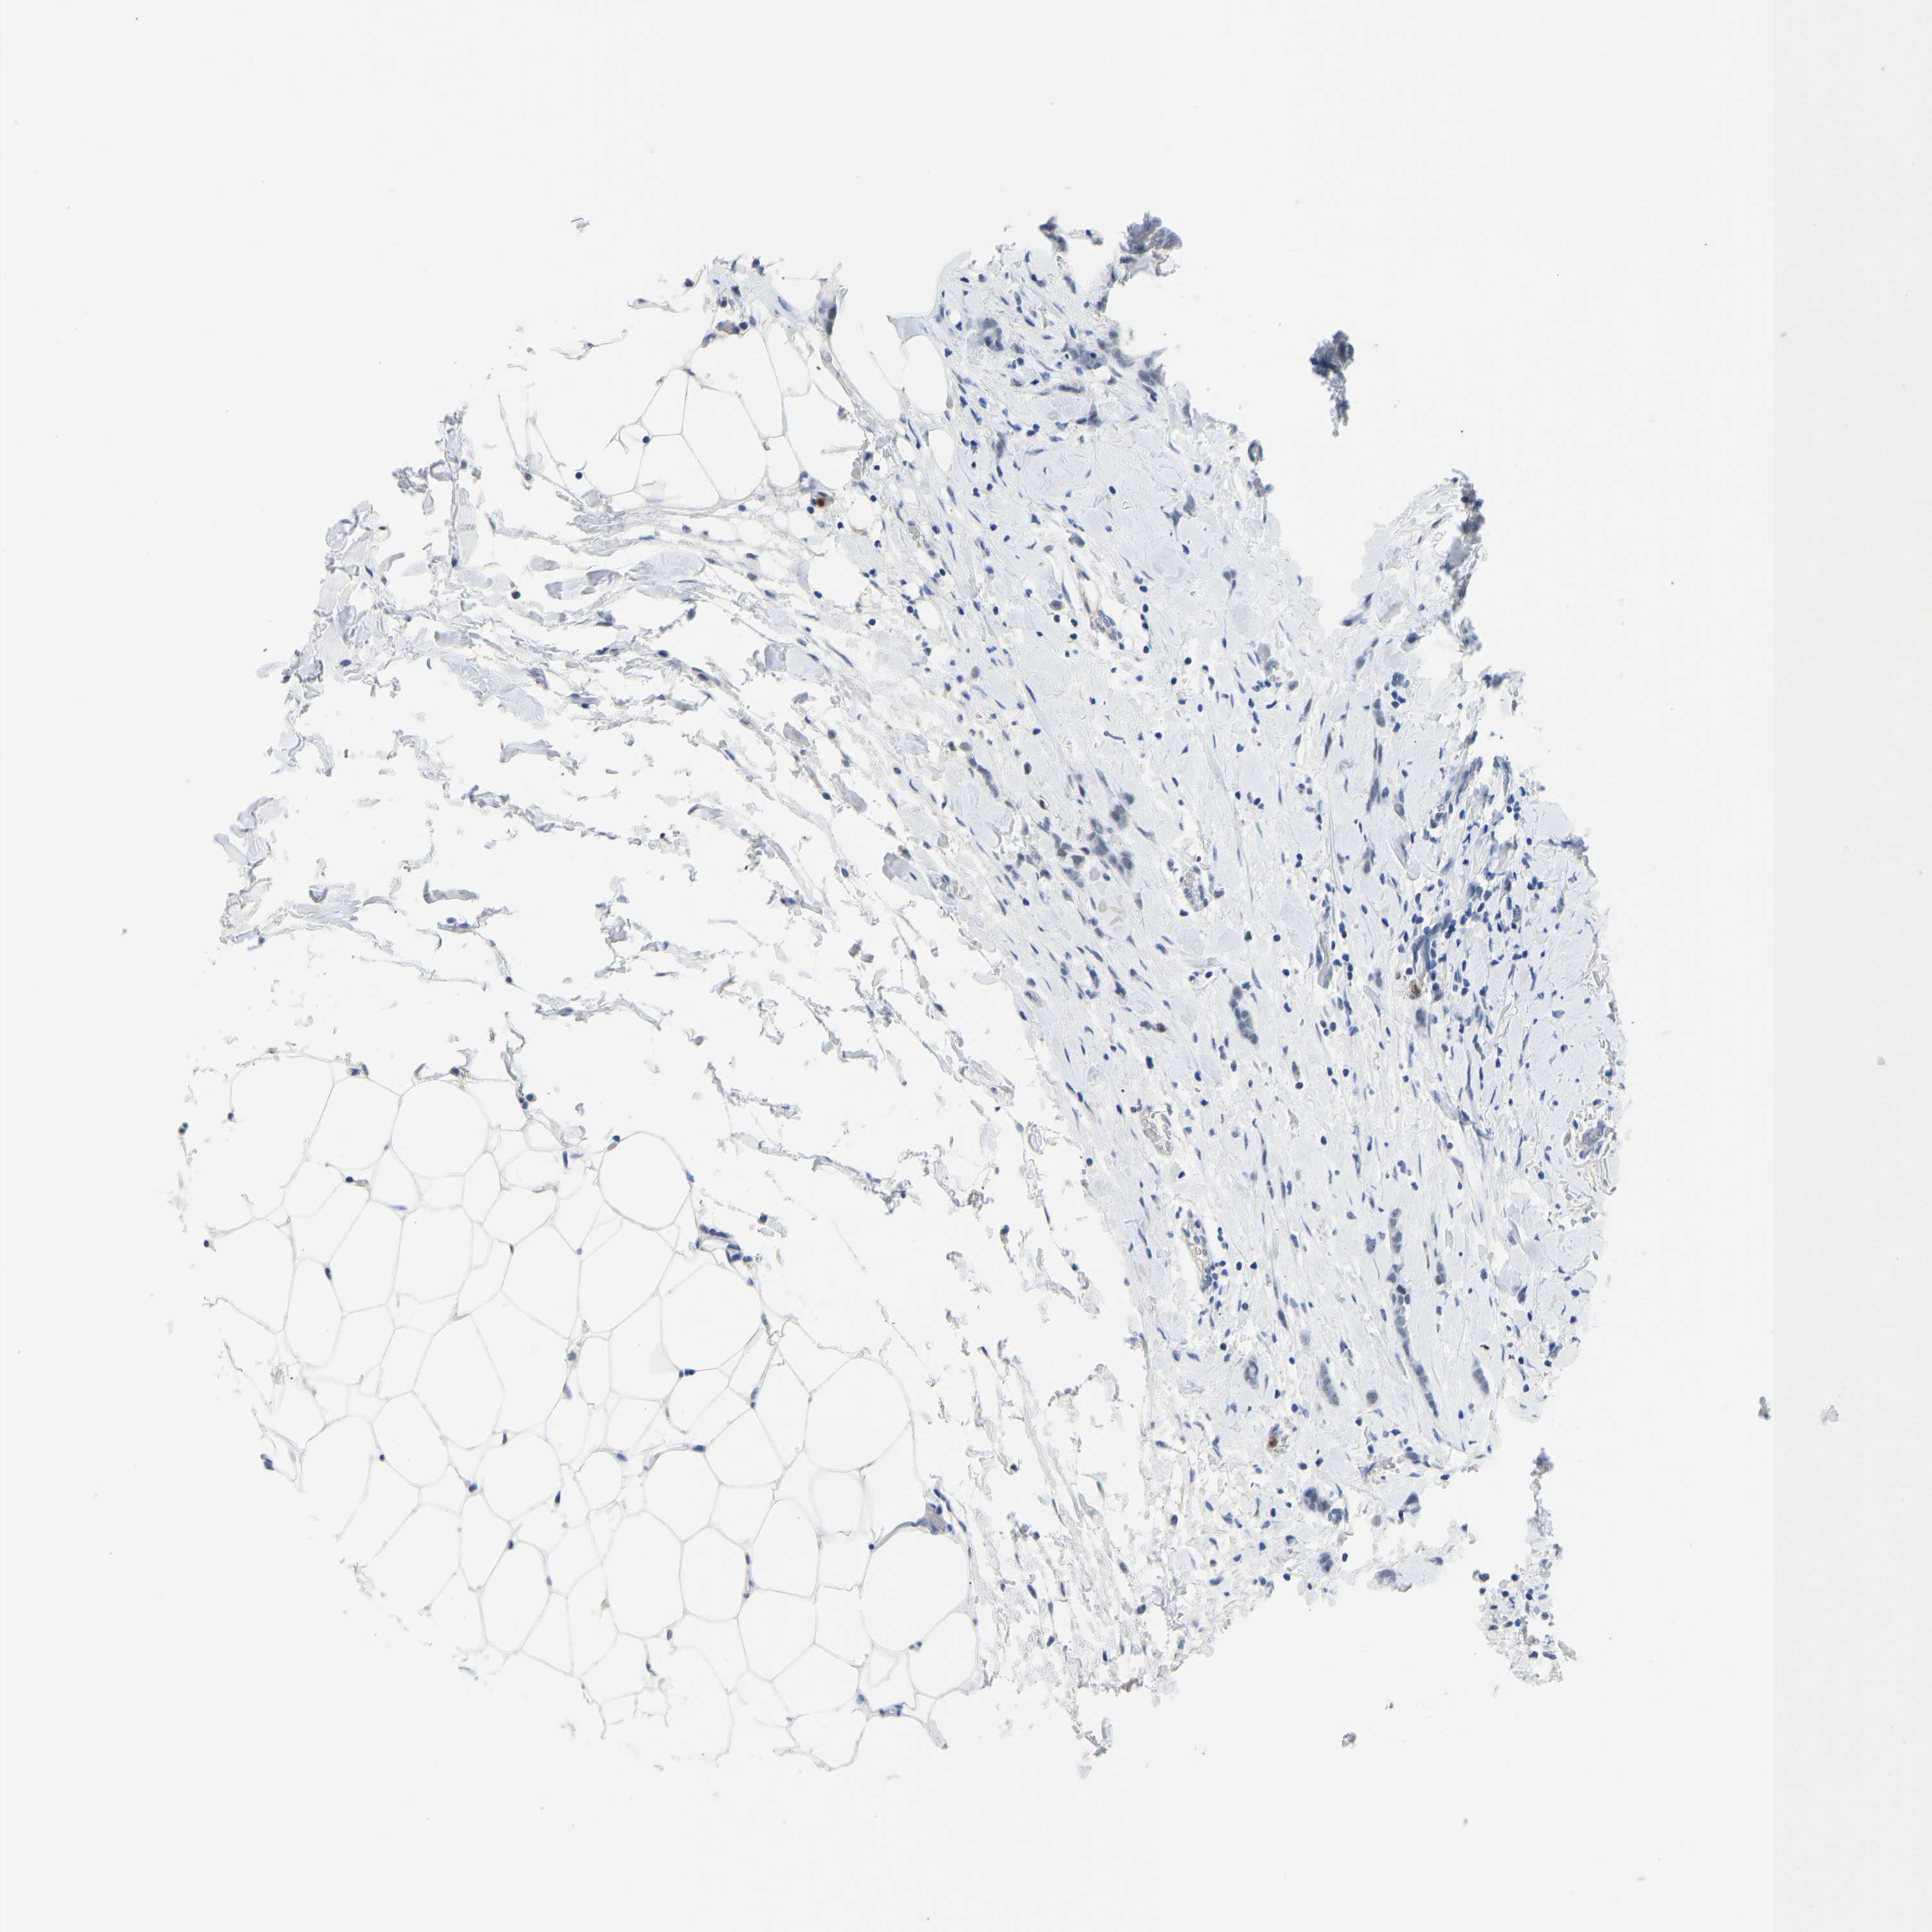

CANCER BREAST CANCER Show tissue menu

BRCA TCGA BRCA VALIDATION PROTEIN EXPRESSION